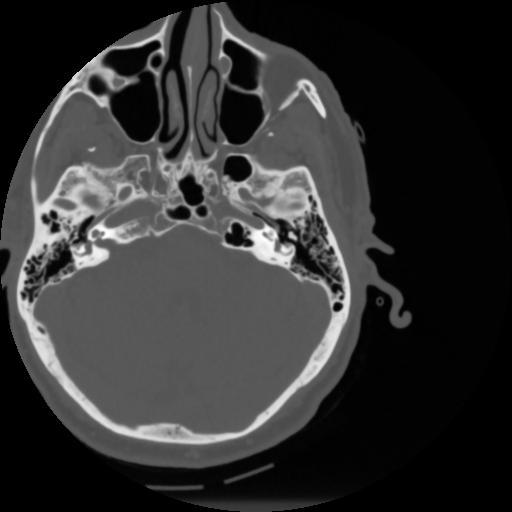

4 CEREBRO,,Vol,0.5,CEREBRO,,